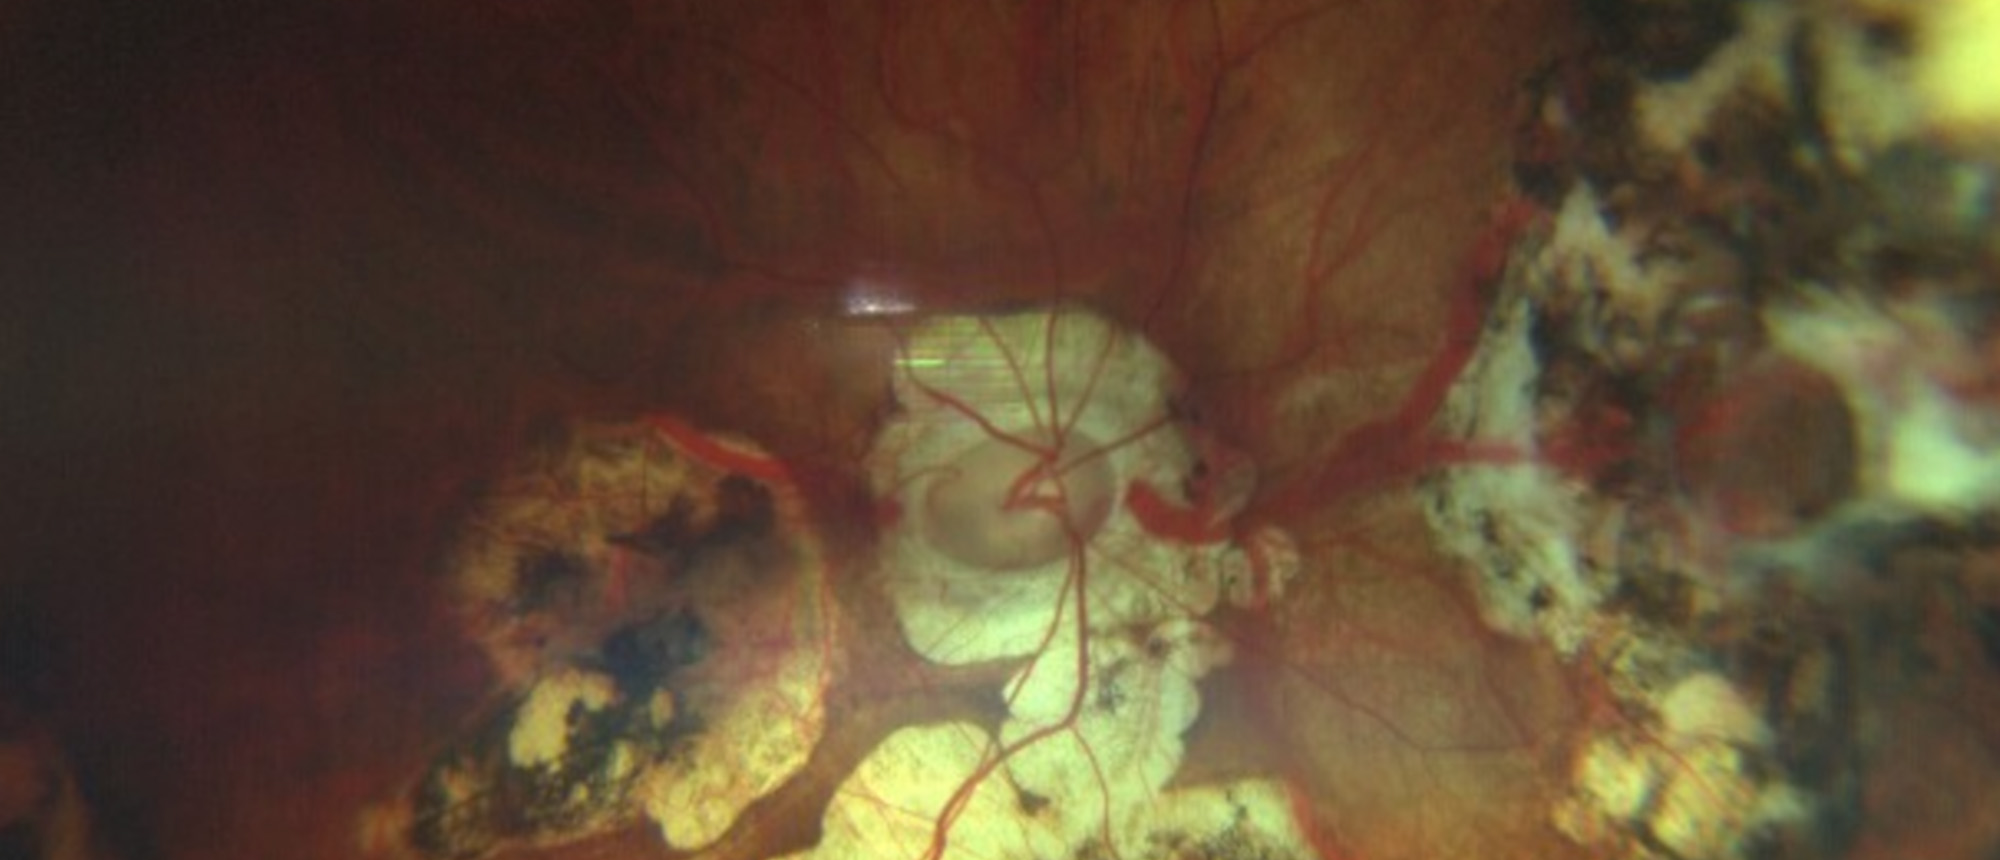

Acute syphilitic posterior placoid chorioretinopathy (ASPPC) is a unique ocular sign of syphilis. It appears as a large, flat, yellowish lesion on the retinal pigment epithelium, typically in the macula. While not seen in every syphilis case, its presence strongly suggests ocular involvement and wa…